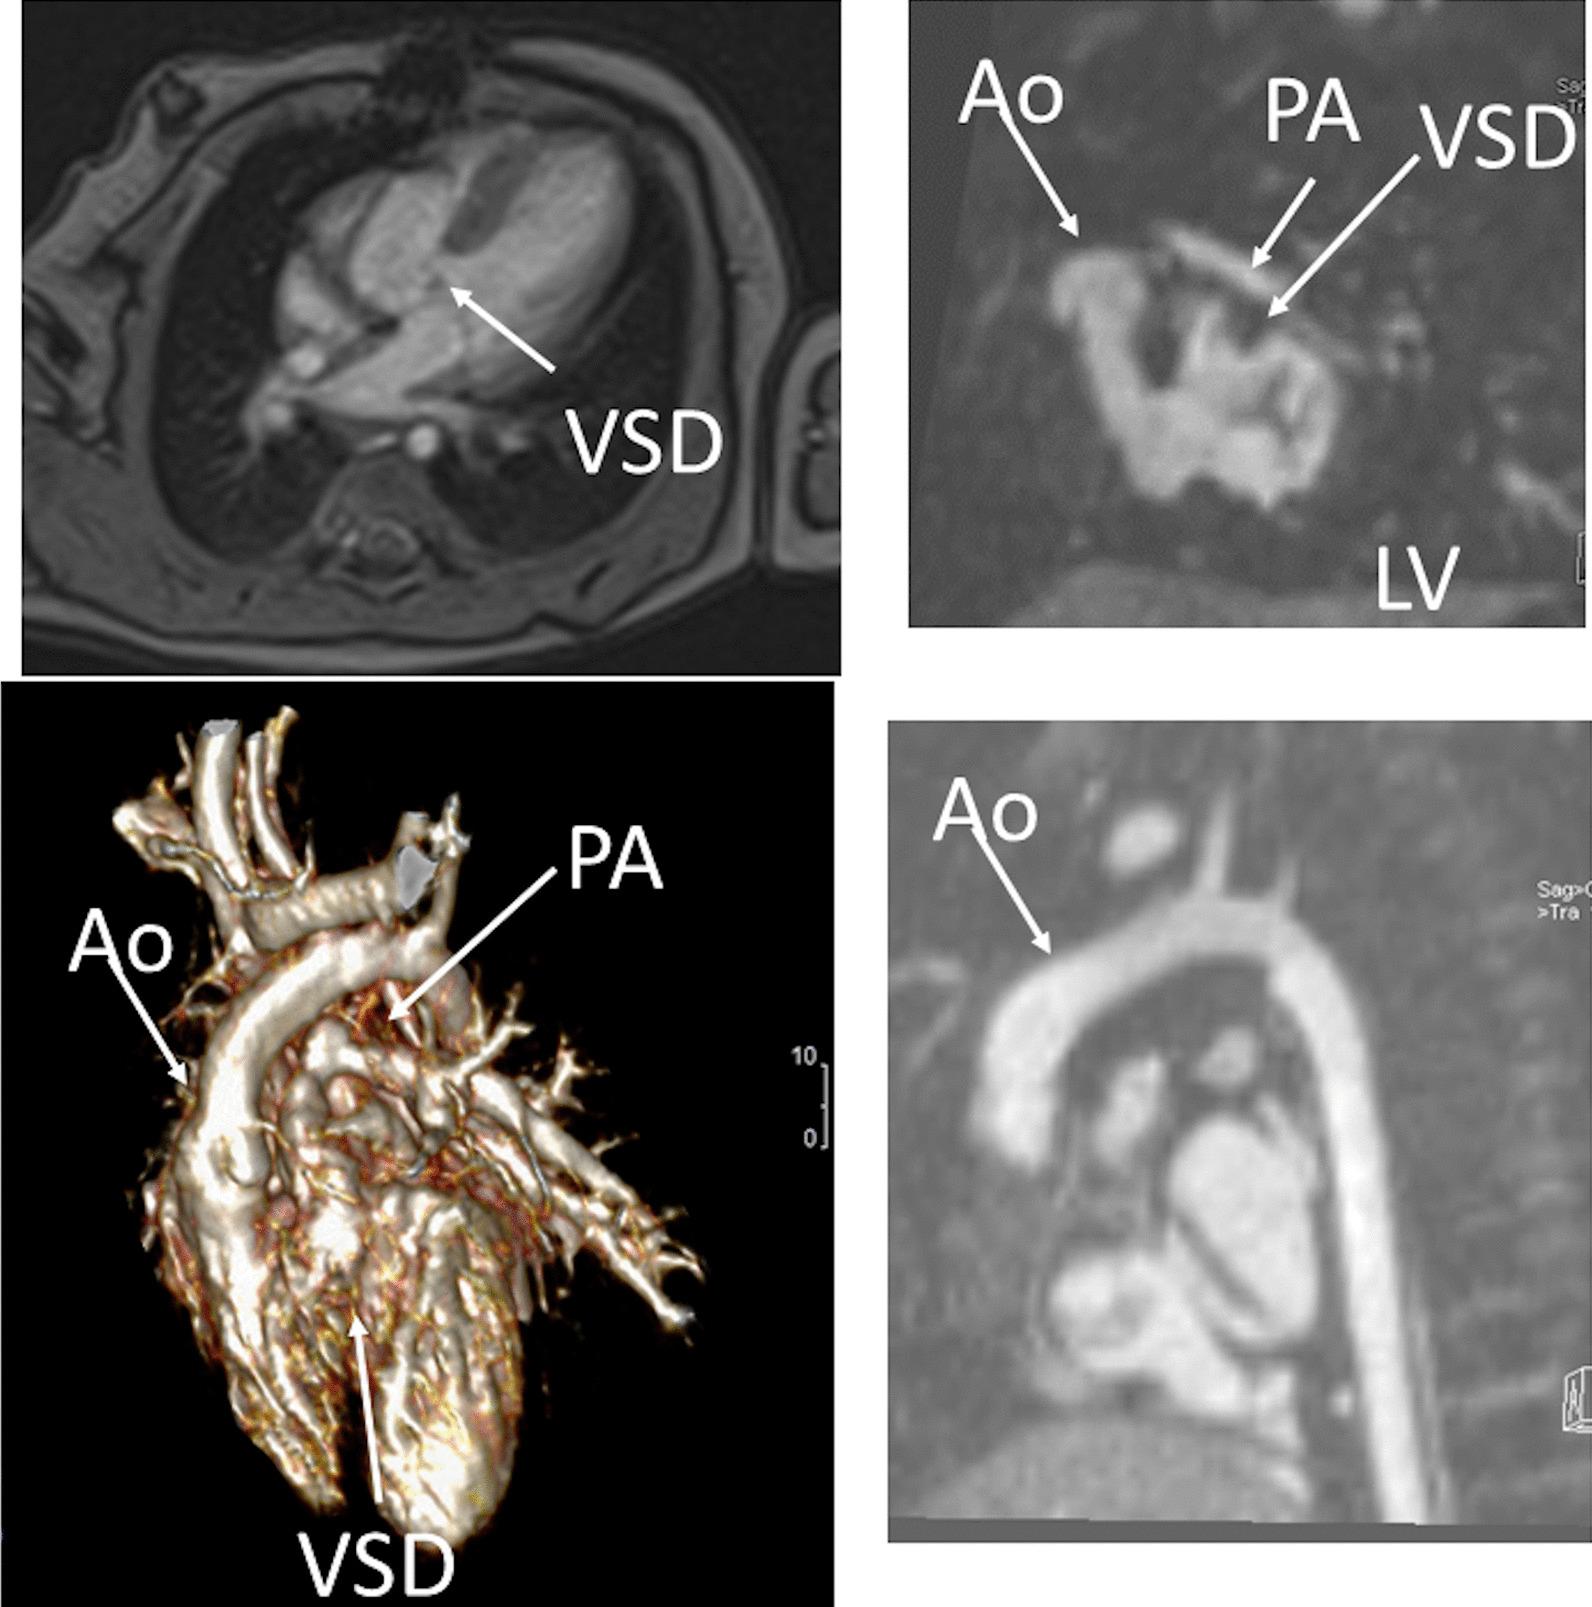

Cardiovascular magnetic resonance (CMR) has been utilized in the management and care of pediatric patients for nearly 40 years. It has evolved to become an invaluable tool in the assessment of the littlest of hearts for diagnosis, pre-interventional management and follow-up care. Although mentioned in a number of consensus and guidelines documents, an up-to-date, large, stand-alone guidance work for the use of CMR in pediatric congenital 36 and acquired 35 heart disease endorsed by numerous Societies involved in the care of these children is lacking. This guidelines document outlines the use of CMR in this patient population for a significant number of heart lesions in this age group and although admittedly, is not an exhaustive treatment, it does deal with an expansive list of many common clinical issues encountered in daily practice.

心血管磁共振(CMR)在儿科患者的管理和护理中已经应用了近 40 年。它已经发展成为评估最小的心脏的宝贵工具,用于诊断、介入前管理和随访。尽管在许多共识和指南文件中提到,但在儿科先天性心脏病和后天性心脏病领域,目前还缺乏一份由众多参与儿童护理的学会共同认可的、最新的、独立的、针对 CMR 使用的大型指南。本指南文件概述了 CMR 在该年龄段的许多心脏病变中的应用,尽管不能说是详尽的治疗方法,但它确实涉及了在日常实践中经常遇到的许多常见临床问题的广泛列表。